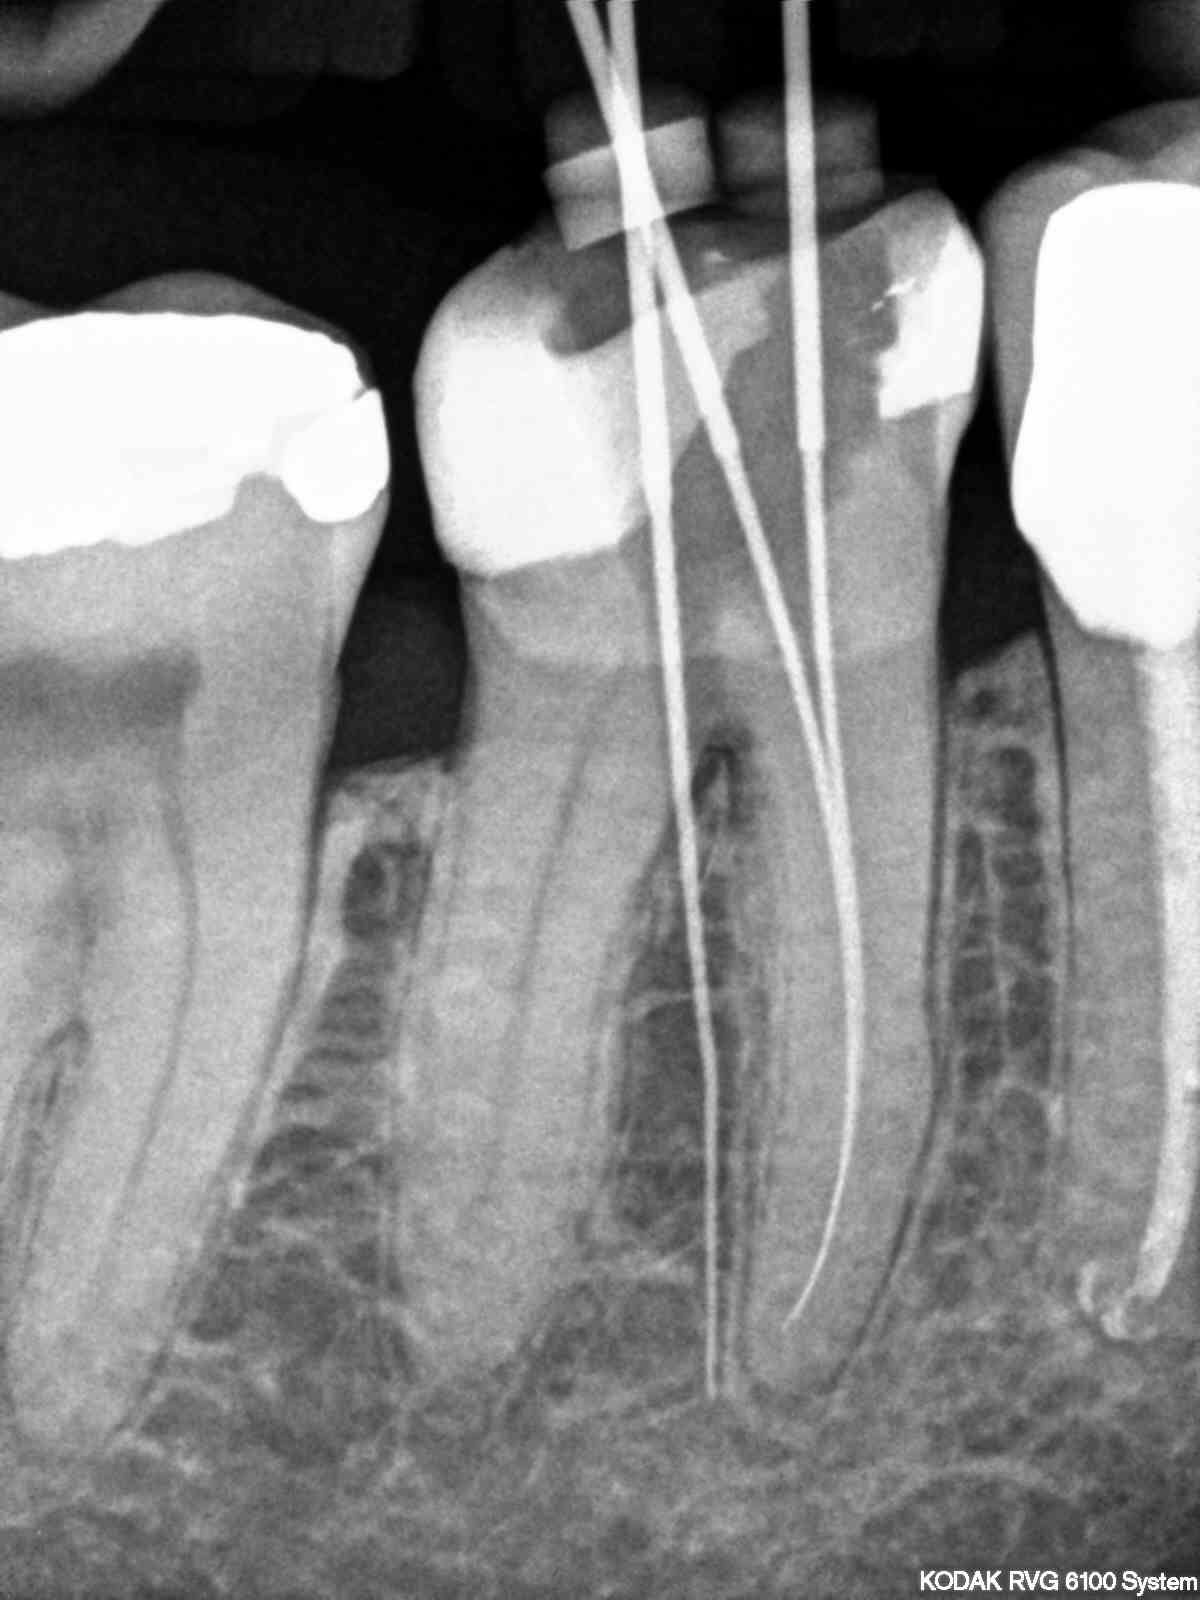

What?? No inlay-core???!!!

T00TH

Joli!

Par contre, il y a peut être une reprise de carie en distale !

Une nouvelle couronne et Go pour 10 ans de plus !